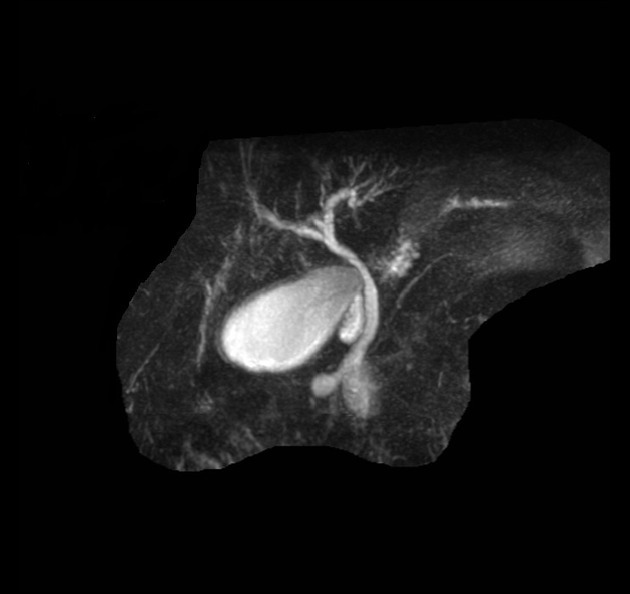

The study is compatible with dilatation of entire extrahepatic bile duct, that’s also known as a true choledochal cyst. Is the type 1 of Todani classification of bile duct cysts.

todani type I

fusiform common bile duct dilation

most common choledochal cyst

tondani type I = fusiform dilation of the CBD